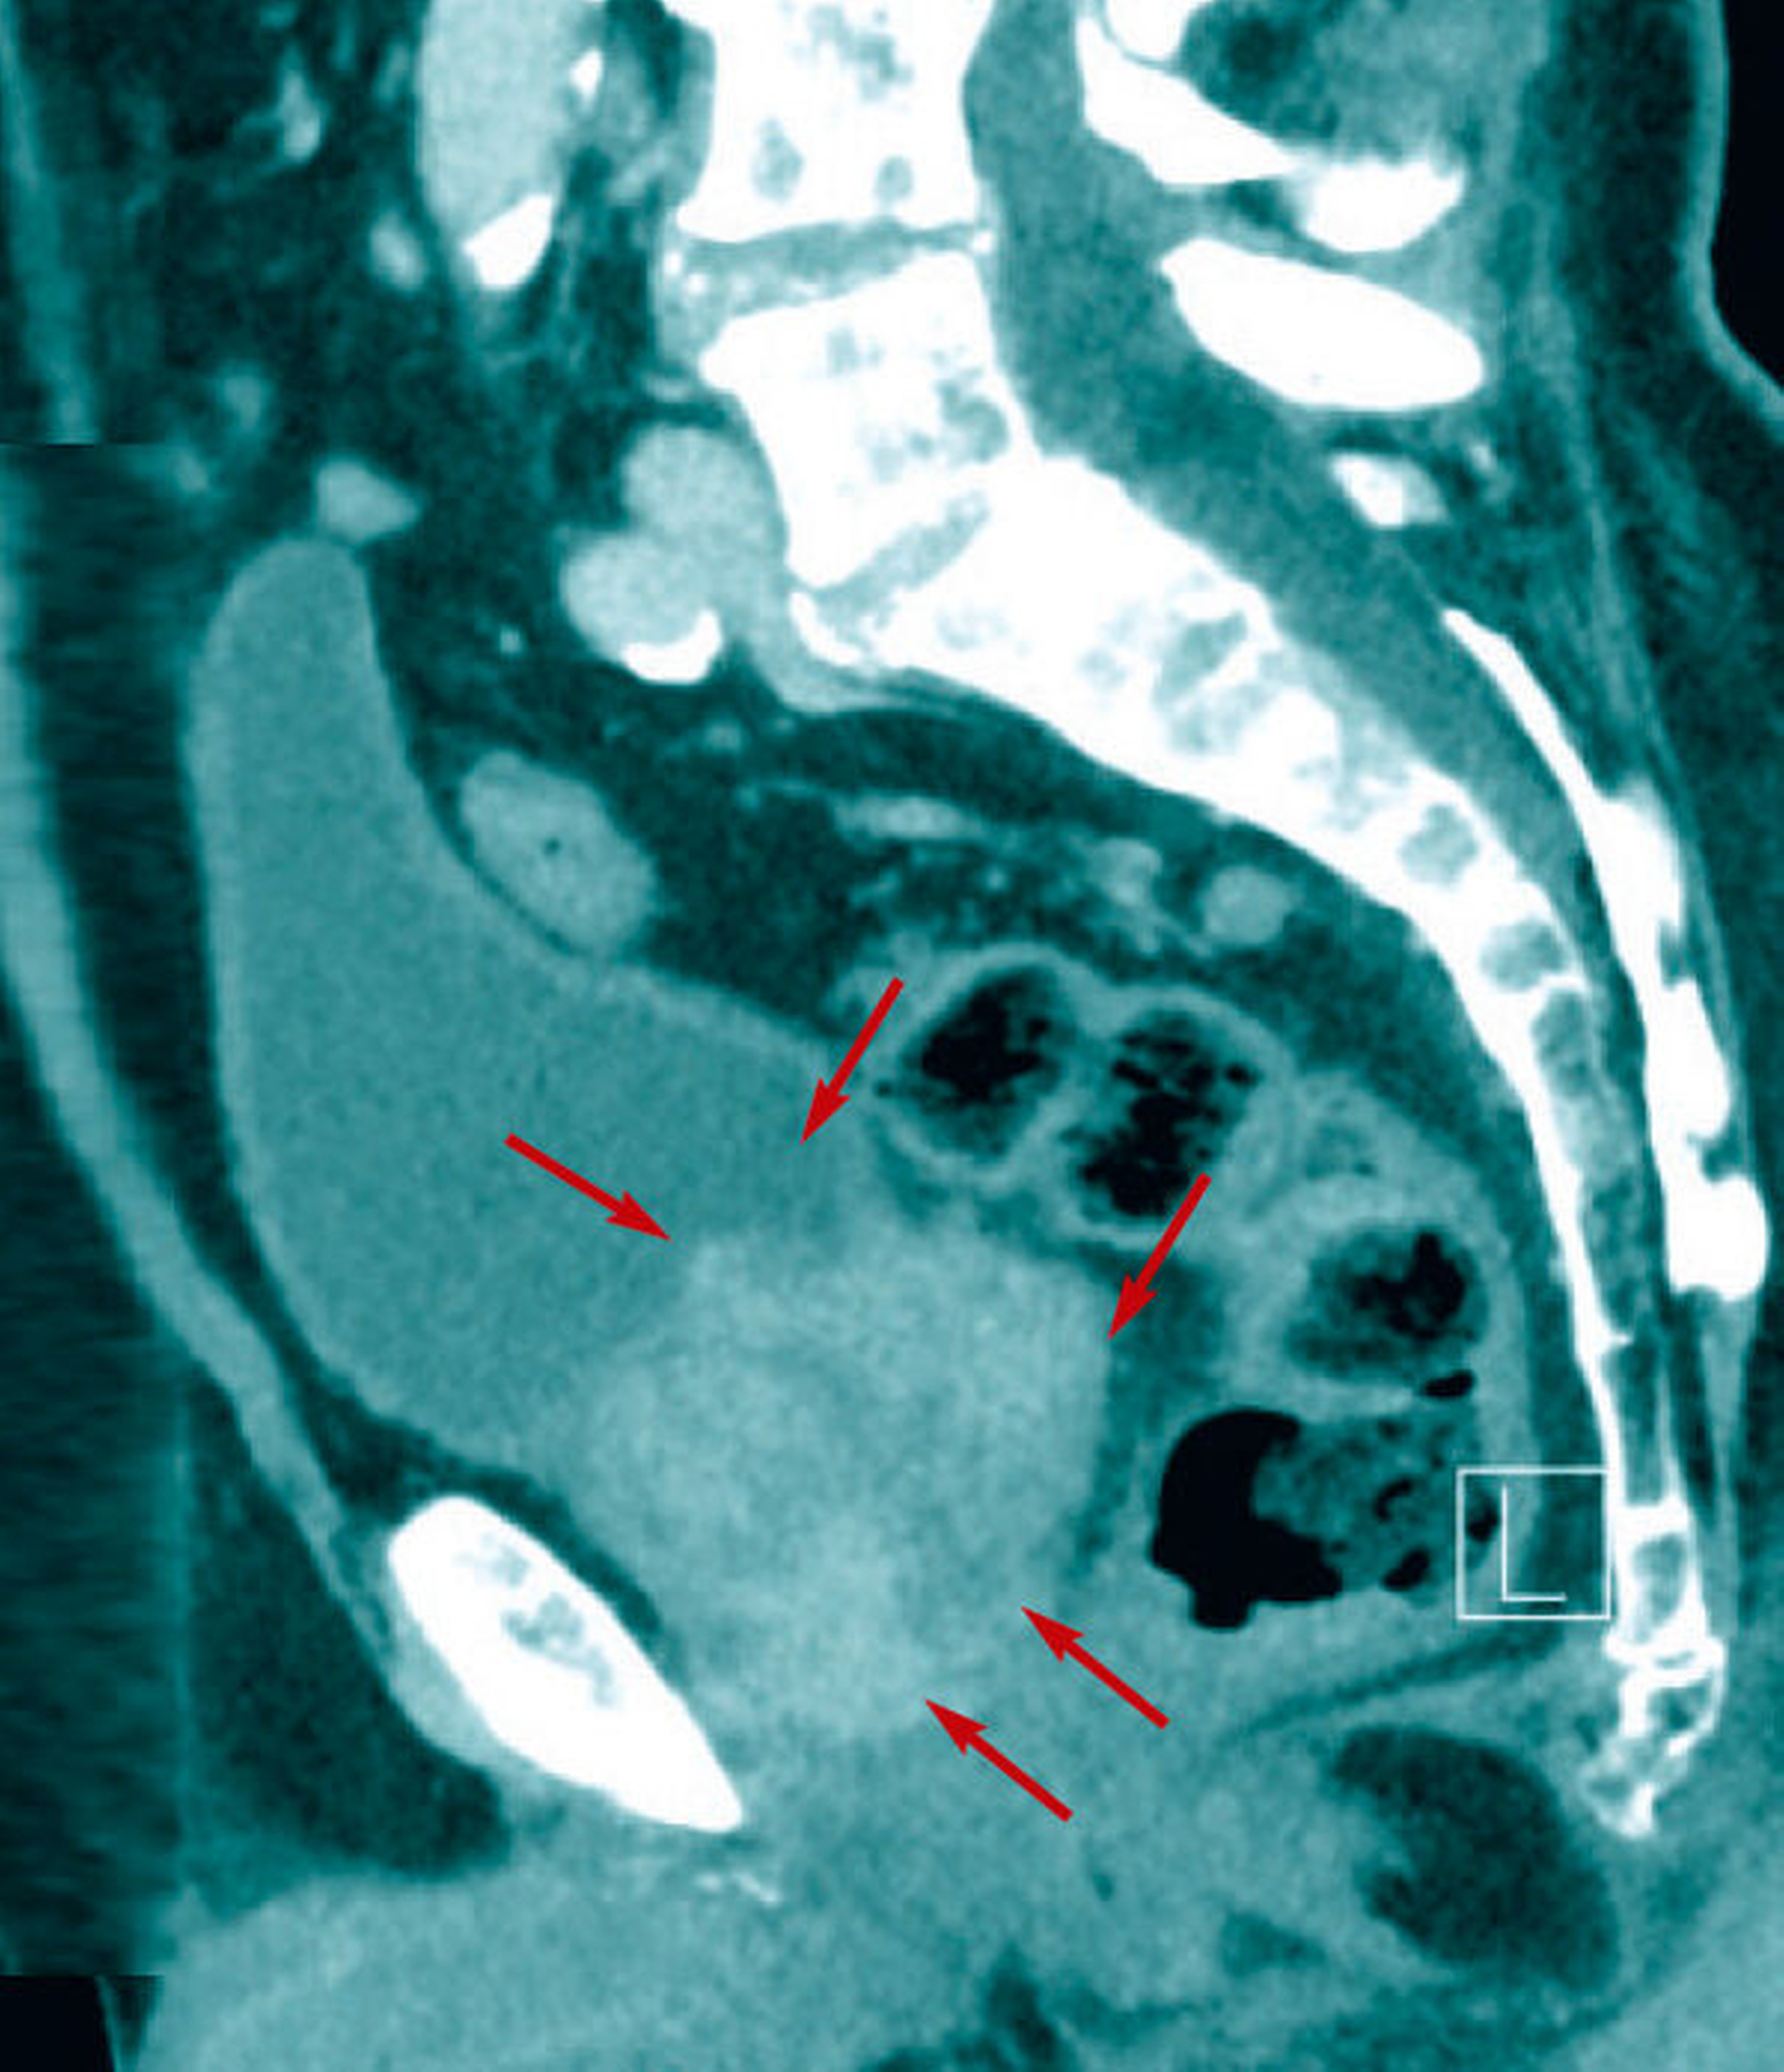

Daraufhin erfolgte umgehend eine Staginguntersuchung (Kopf/Hals/Thorax/Abdomen/Becken) mittels Computertomografie (CT) mit Kontrastmittel. Neben der bereits bekannten Raumforderung im rechten Unterkiefer bestätigte sich auch radiologisch der Verdacht auf ein Prostatakarzinom als Primarius (Abbildungen 4 und 5). Dieses zeigte sich klinisch im Stadium G2 mit Lymphgefäßinfiltration. Zusätzlich zu der mandibulären Metastasierung zeigten sich multiple disseminierte osteolytische Veränderungenim Bereich der Wirbelsäule, die hochgradig metastasensuspekt waren (Abbildung 6).